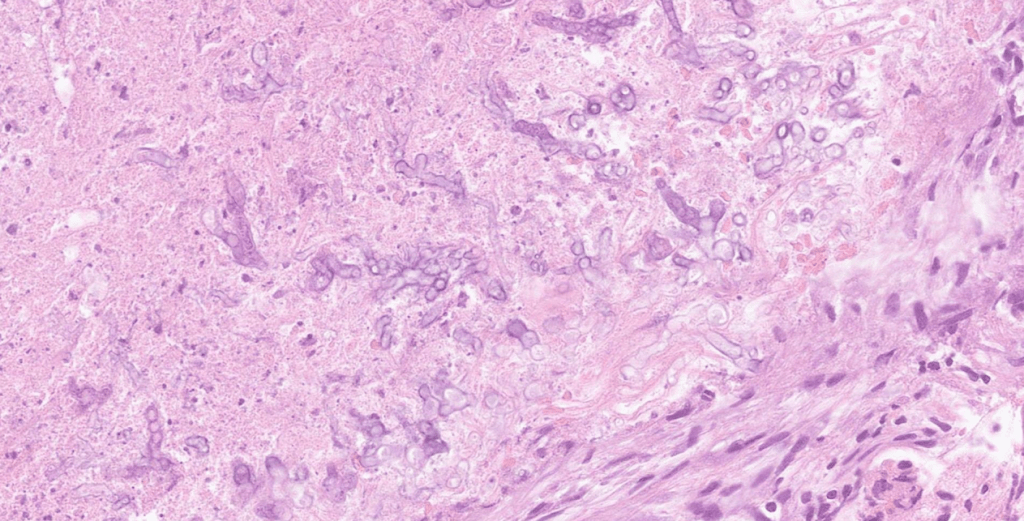

此外,由於黴菌的形態學在治療後或壞死組織中可能出現形態變化,常會使病理判讀變得更具挑戰性。在本次個案中,最初病理判讀為 Actinomyces 與 Mucorales,但後續實驗室培養與 NGS 檢測結果顯示黴菌為 Aspergillus fumigatus,也提醒我們在臨床診斷上仍需整合多種檢查結果。分子診斷技術的早期介入,不僅能夠更精準地確立致病菌,也可能爭取寶貴的治療時間,對於侵襲性黴菌感染的處置具有重要意義。

最後,感謝感染科、耳鼻喉科與神經外科醫師在準備這次 MM-C 期間的協助與討論,也感謝病理科醫師教導我觀察組織玻片,讓我更了解不同染色方式的目的與判讀重點。再次感謝我的指導老師吳丁樹醫師在病歷整理、臨床討論與報告架構上的建議,使我在這次報告中獲得寶貴的臨床經驗與反思,也讓我對侵襲性黴菌感染的診斷與治療有更深入的理解。